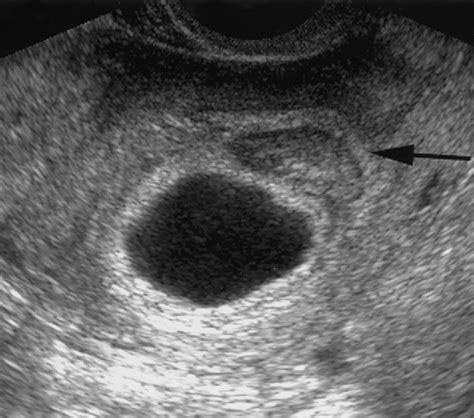

Ultrasound Determination Embryo seeable Empty gestational sac

Diagnosing is almost forever support via transvaginal echography. A doctor will appear for the front of a gestational sac and, depending on the gestation period, look for the conceptus within that sac. If the sac is empty and measure a certain size, the diagnosing of a spoilt ovum is confirmed.